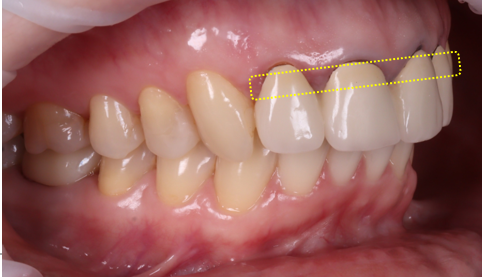

촬영 : 251030

최종적으로 완성된 지르코니아 크라운은 빛이 통과하면서 자연스러운 투명감이 느껴졌어요.

경계 부위가 검게 변해 있던 기존 모습이 생각나지 않을 정도로 큰 변화를 느낄 수 있었는데요.

환자분께서 거울을 보며 활짝 웃으셨던 순간이 아직도 기억납니다ㅎㅎ 개별 크라운으로 제작되어 치실 사용이 가능하여 사용법도 알려드렸습니다.

또한 잇몸 선도 시간이 지나며 점점 안정되기 때문에 시간이 지나면서 더 자연스러워질 거라고 설명을 드렸죠ㅎㅎ

틀어진 치아 축도 얼굴 앞면을 바라보도록 제작했죠.